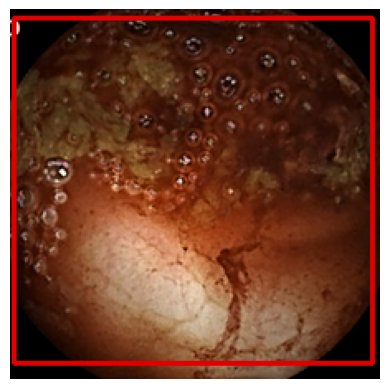

This study presents an integrated deep learning model for automatic detection and classification of Gastrointestinal bleeding in the frames extracted from Wireless Capsule Endoscopy (WCE) videos. The dataset has been released as part of Auto-WCBleedGen Challenge Version V2 hosted by the MISAHUB team. Our model attained the highest performance among 75 teams that took part in this competition. It aims to efficiently utilizes CNN based model i.e. DenseNet and UNet to detect and segment bleeding and non-bleeding areas in the real-world complex dataset. The model achieves an impressive overall accuracy of 80% which would surely help a skilled doctor to carry out further diagnostics.